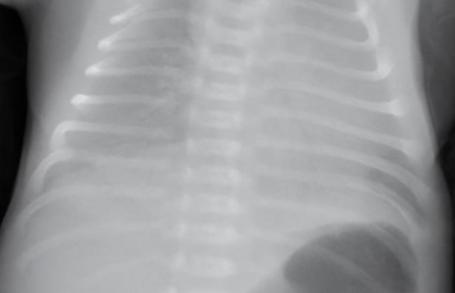

有些網友在網上問什么是白肺,白肺的意思就是肺變成了白色,一般重癥肺炎才會引起白肺病,當出現了白肺病通過X,片檢查會,顯示肺部呈現一大片的白色狀,這就意味著病入膏肓,死亡率極高,對于這一次到底是誰制造的謠言,又是什么原因讓謠言四起,希望相關部門嚴格調查此事。